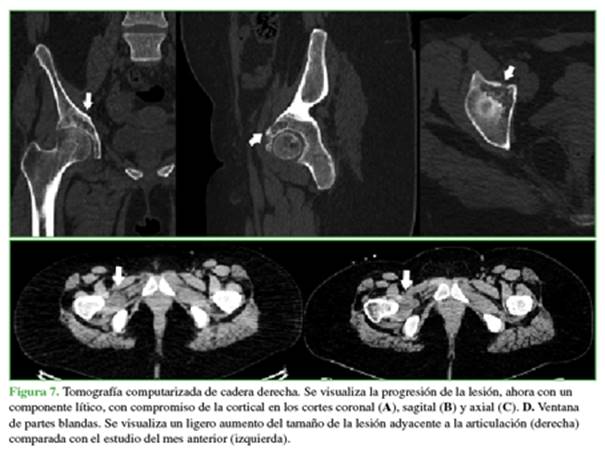

Tras descartar un cuadro respiratorio agudo y un proceso neoplásico en la cadera, se realizó una interconsulta con el Servicio de Reumatología. Se solicitó una nueva evaluación de la cadera con una tomografía (Figura 7).